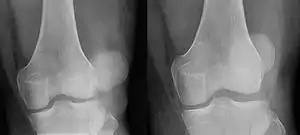

![]() | |

| Patellar luxation on radiograph: Left before, right after reduction; after reduction, the patella is still displaced. | |